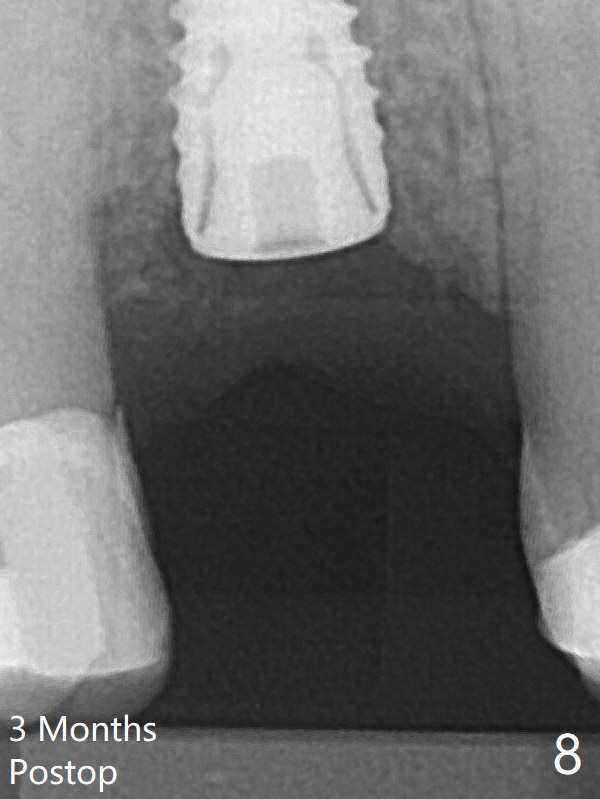

术后三个月根尖片显示骨粉减少(图八)。不可吸收膜脱落可能造成骨粉流失。应该做减张缝合。树脂敷料,而不是牙周敷料。其实缝合压扁骨粉,愈合或者细长的修复基台有支撑,减张作用。后面讨论。中央血供不够,伤口裂开。周围骨粉能成活就好。